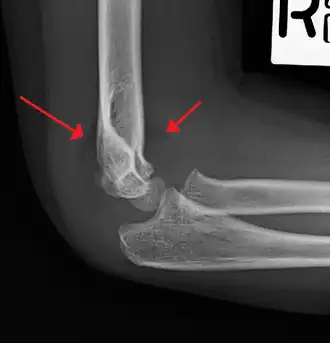

Anterior and posterior sail sign in a child who has a subtle supracondylar fracture -